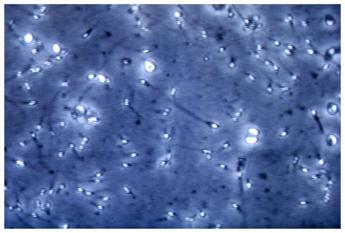

(Adnkronos) – Un gene mancante. Potrebbe essere l'assenza di una proteina strategica a spiegare l'infertilità maschile. Un'assenza che ha conseguenze sugli spermatozoi, i quali si ritrovano senza connessione tra la coda e la testa. E' la tesi avanzata da ricercatori dell'università di Göteborg in Svezia. Gli scienziati hanno identificato una nuova proteina, da loro soprannominata 'MC2', che sembra svolgere un ruolo cruciale nella formazione di sperma capace di 'nuotare'. I topi privi del gene incriminato – quello cioè che controlla la proteina MC2 – non sono in grado di produrre prole. L'ipotesi apre la strada allo studio di nuovi metodi diagnostici e trattamenti, ma anche alla ricerca su un possibile futuro contraccettivo maschile. La proteina che ha attirato l'attenzione degli esperti risulta necessaria per far sì che testa e coda degli spermatozoi 'si parlino'. "La connessione si trova nel 'collo' della testa dello sperma e facilita il movimento e la funzione coordinati mentre lo sperma nuota verso l'ovulo. Certamente, la coda e la testa verranno create perfettamente anche senza tale connessione, ma senza alcun risultato, poiché non saranno in grado di raggiungere il loro obiettivo", afferma Kexin Zhang, dottoranda nel Dipartimento di chimica e biologia molecolare dell'università di Göteborg. Gli esperimenti condotti sui topi hanno indicato a Kexin Zhang e colleghi che la produzione della proteina MC2 era controllata da un gene specifico nel genoma. Ironia della sorte, questo appare senza importanza invece per le femmine. Il gene infatti non si trova sul cromosoma sessuale e non ha avuto alcun impatto sulla capacità delle femmine di produrre prole. Quando è stato rimosso nei topi maschi utilizzando delle 'forbici genetiche', i ricercatori hanno visto che smettevano di produrre la proteina e diventavano completamente sterili. È già noto che i fattori genetici sono responsabili del 15-30% dell'infertilità maschile. Quella identificata dai ricercatori potrebbe essere una causa che rientra nella categoria. "La mia ricerca ha contribuito a migliorare la comprensione delle cause dell'infertilità dovuta all'assenza della testa degli spermatozoi, nota come sindrome degli spermatozoi acefali. Finora la causa di questa diagnosi era sconosciuta", evidenzia Kexin Zhang. La scoperta della proteina MC2 fornisce nuove informazioni sulla struttura molecolare delle cellule spermatiche che poi si sviluppano negli spermatozoi. I ricercatori saranno in grado di studiare ulteriormente queste informazioni, si spiega nel lavoro svedese. "Si stima che circa il 15% di tutte le coppie eterosessuali abbiano problemi ad avere figli. In circa la metà dei casi l'uomo è responsabile dei problemi. Spero che la nostra ricerca porti alla fine a nuovi metodi diagnostici e nuovi trattamenti per l'infertilità maschile. Potrebbe anche essere possibile – conclude Kexin Zhang – creare un contraccettivo maschile disattivando questo gene". —cronacawebinfo@adnkronos.com (Web Info)